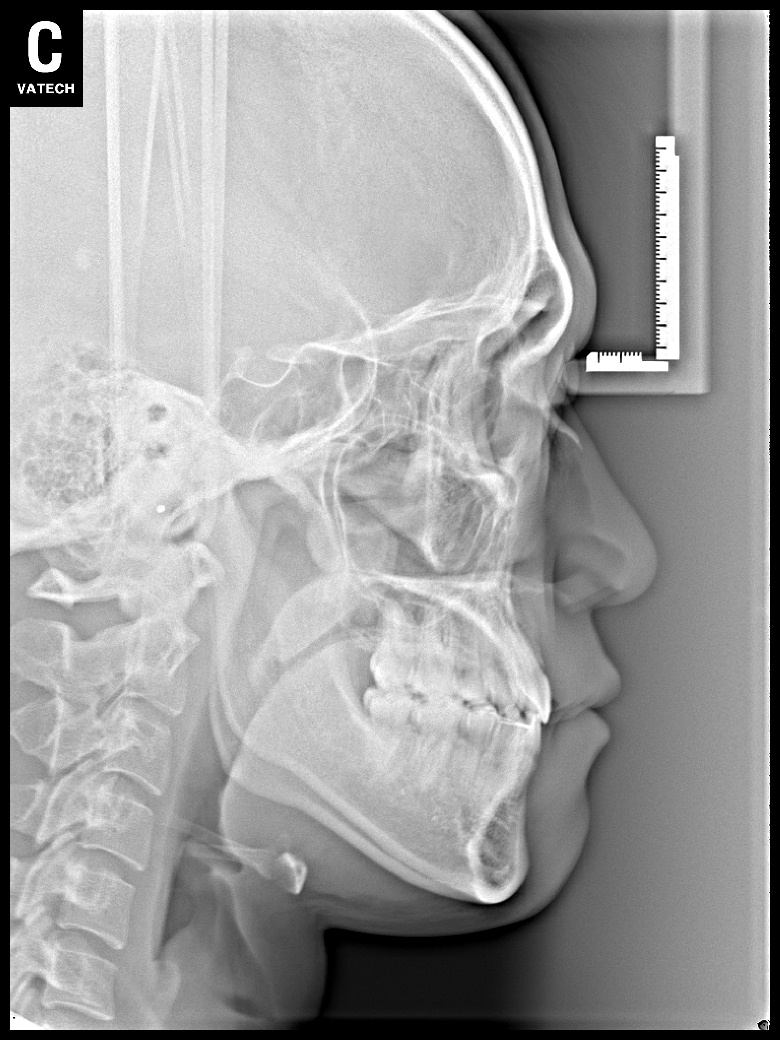

치료 후 사진입니다.